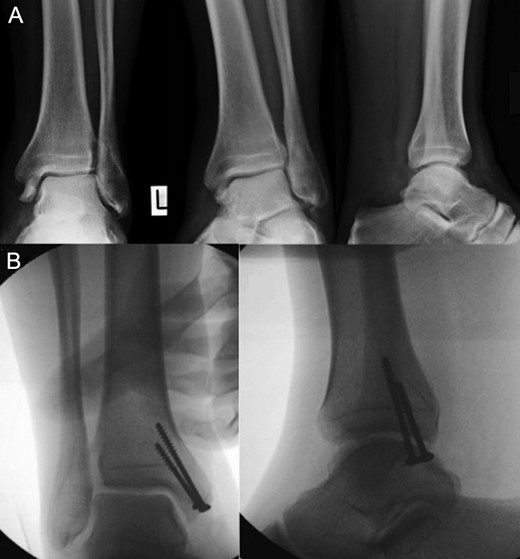

Plain radiographs of anteroposterior, mortise and lateral views revealed a fracture of the medial malleolus with no other bony injuries (Fig. 1). Surgery was performed with the patient under general anaesthetic in a supine position with an above-knee tourniquet. A medial incision was made along the medial malleolus, inline with the tibialis posterior tendon. The flexor retinaculum was incised in order to expose the tibialis posterior tendon. The periosteum of the posteromedial fragment was then elevated, and the tibialis posterior tendon was retracted with an intact tendon sheath posterolaterally. This enabled the reduction of the fracture under direct vision. Two 4.0 cannulated screws were then inserted with countersink to stabilize the fracture, and the periosteum was repaired over the top of the screw ends. The flexor retinaculum was then repaired meticulously, followed by subcutaneous and subarticular closure of the wound.

Plain radiographs of anteroposterior, mortise and lateral views revealed a fracture of the medial malleolus with no other bony injuries. A (above): before surgery, B (below): after surgery.